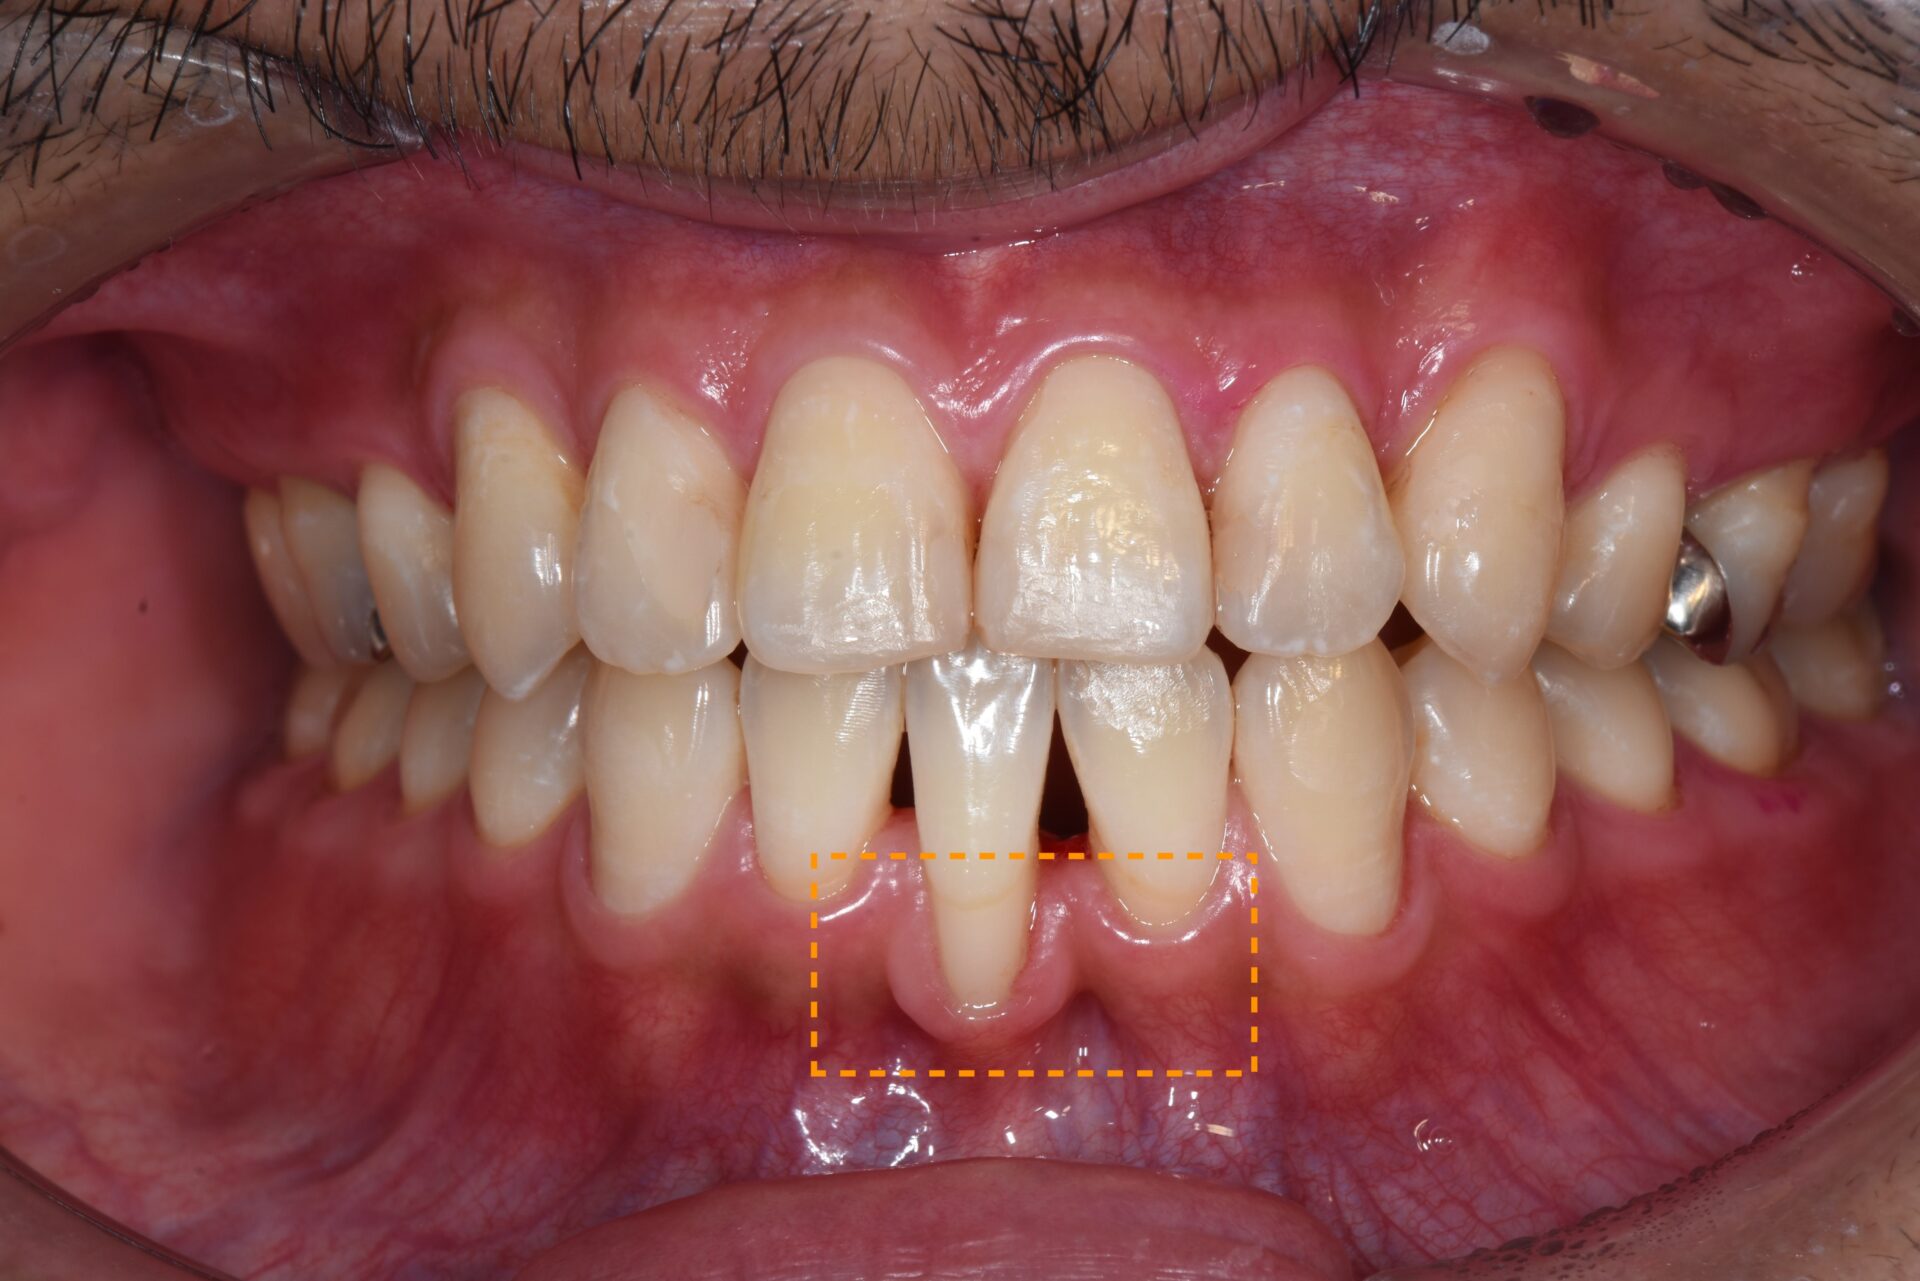

矯正治療後、下顎前歯部の歯肉が退縮して歯根が露出し、見た目と機能の両面でお悩みでした。歯肉は非常に薄く、付着歯肉も不足しており、ブラッシング時に傷つきやすく、清掃が困難な状態でした。そのため、炎症を繰り返しており、審美的にも不均衡が見られました。長期的に歯周組織を安定させるには、外科的な介入が必要と判断しました。

3か月後には付着歯肉の幅がしっかりと増加し、炎症が改善。歯肉の厚みと付着歯肉の幅が増加し、ブラッシング時の出血や痛みが改善され、審美的に自然で調和の取れた歯肉ラインを獲得。長期的に安定した歯周組織環境を確立することができた。

術前

術前1ヶ月

術前3ヶ月